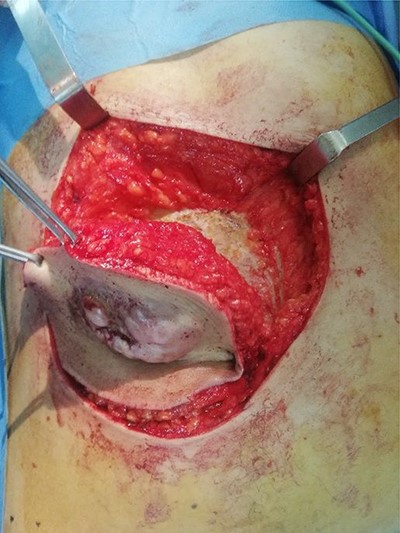

A 45-year-old woman complained of the occurrence of a small cutaneous lesion on the AAW evolving over the past precedent 3 years. The swelling volume had progressively increased. The physical examination revealed an oval mass with regular borders and a polylobed surface; the lesion was localized at the supra-umbilical level of AAW, and slightly lateralized on the right with dimensions of 5 cm by 3 cm (Fig. 1). The palpation revealed a hard and fixed swelling on the skin. However, it remains freely mobile regarding the deeply musculoaponeurotic plane. The histopathological findings on the skin biopsy were consistent with DFSP. The thoracic–abdominopelvic computed tomography (CT) scan did not show any metastatic lesions. The abdominal CT sections showed a well-defined enhancing soft tissue density lobulated lesion measuring 5.8 × 1.5 cm and arising from the AAW. The lesion presented a discreetly heterogeneous enhancement. It infiltrated subcutaneous tissue without any involvement of the musculoaponeurotic plane which remained distant from the lesion (Fig. 2). The patient underwent WLE with minimal macroscopic safety margins of 3 cm from the visible and palpable limits of the tumor (Fig. 3). The resulting defect was repaired with primary closure by advancing the adjacent tissue. Indeed, the cutaneous and subcutaneous tissue under the wound caudal edge was raised off anterior abdominal aponeurosis which facilitated flapping advancement and wound-free-tension coverage (Fig. 4a). We obtained an acceptable esthetic result in the form of a transverse mid-abdominal scar (Fig. 4b). The recovery was simple. The specimen histopathology revealed a characteristic of DFSP appearance with spindle cells in a storiform arrangement (Figs 5 and 6). The immunohistochemistry confirmed the diagnosis by revealing cluster differentiation 34 (CD 34) expression (Fig. 7). The margins are microscopically safe. The final decision of the multidisciplinary meeting consisted of surveillance. After 4 years of follow-up, no locoregional or distant recurrence was observed.

Per-operative view showing the resulting wound defect (a) repaired by primary closure (b)